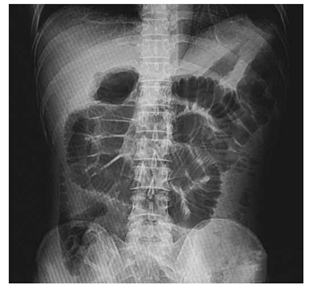

Homem de 39 anos procurou o serviço médico em duas ocasiões na mesma semana por parada de eliminação de gases e fezes, distensão abdominal importante, náuseas e vômitos biliosos há 4 dias. No segundo atendimento, refere piora da dor nas últimas 12 horas. Ao exame físico, observa-se cicatriz mediana ampla (cirurgia prévia por trauma abdominal). No primeiro atendimento, os ruídos hidroaéreos estavam aumentados, mas agora se encontram diminuídos. A radiografia de abdome em posição supina mostra dilatação importante de alças de intestino delgado e ausência de gás nas porções distais do cólon e reto (imagem demonstrada a seguir).

Enunciado 4925944-1

( https://www.shutterstock.com/pt/g/Tomatheart)

Esse quadro aponta para o seguinte diagnóstico: